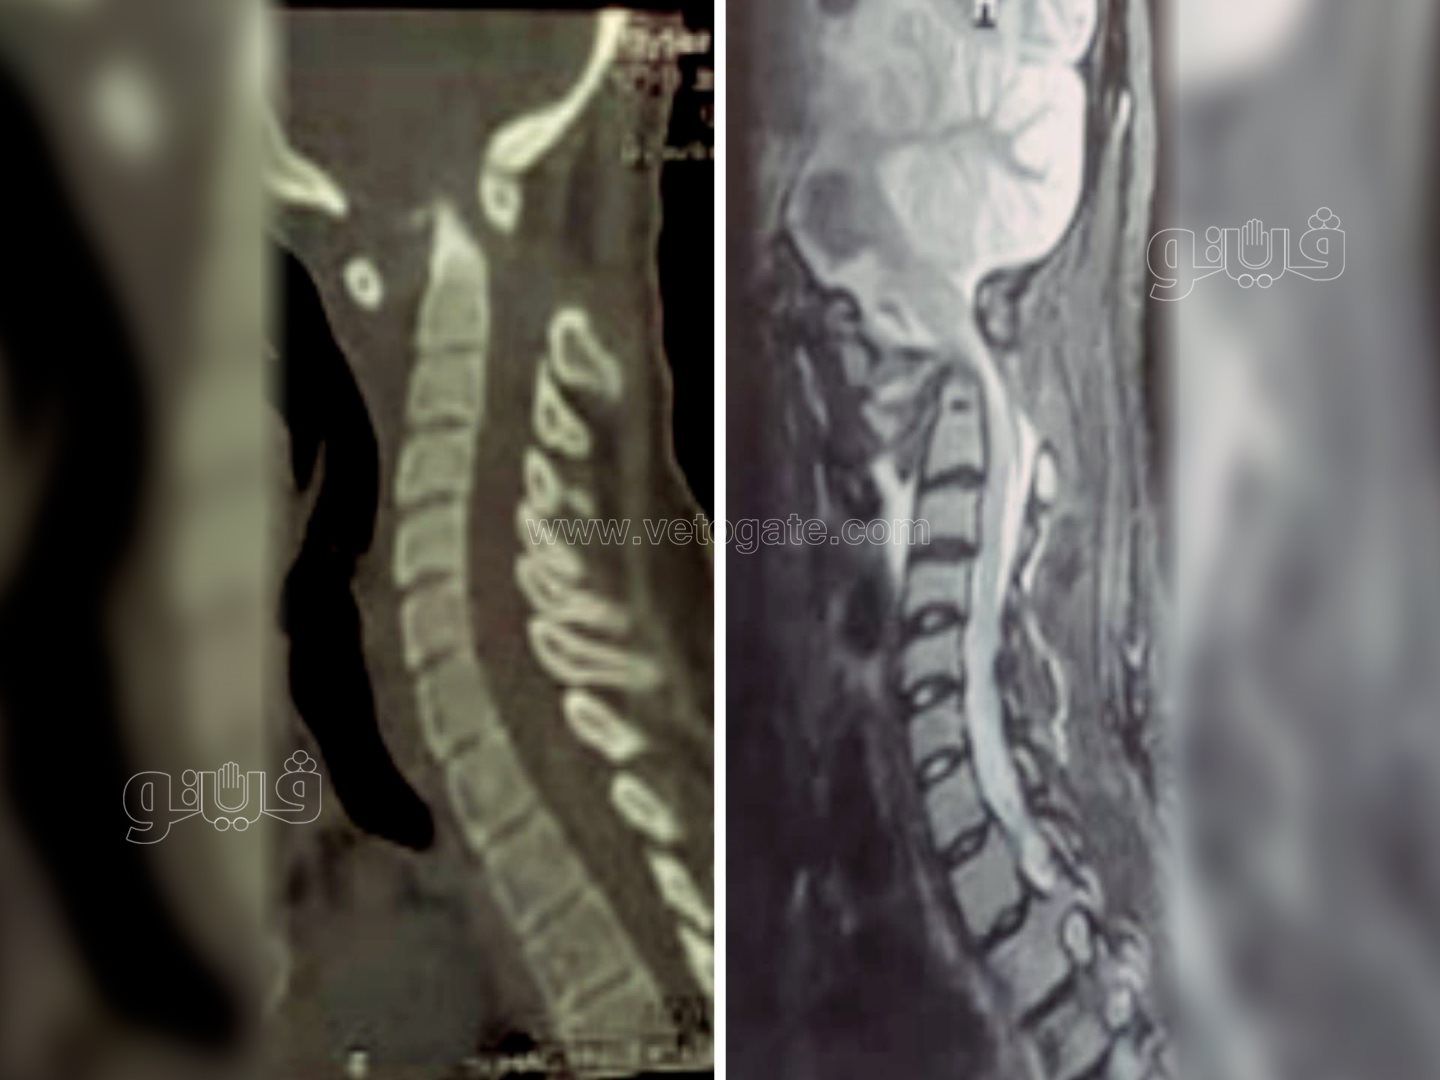

صرح الدكتور مصطفى عبد الخالق رئيس جامعة سوهاج أن قسم جراحة المخ والأعصاب بالمستشفى الجامعي نجح في إجراء تدخل جراحى نادرًا ويعد الأول من نوعه في صعيد مصر، لفتاة تبلغ من العمر ١٨ عامًا، وتعاني من مرض خلقى الانغماس القاعدى مع عدم ثبات قاع الجمجمة فى الاتصال بالفقرات العنقية، وهي من الحالات النادرة الحدوث، حيث أدى هذا المرض إلى إصابة الفتاة بشلل رباعي حاد نتيجة الضغط على الحبل الشوكي وجذع المخ بقاع الجمجمة.

وقال الدكتور مجدي أمين القاضي عميد كلية الطب البشري ورئيس مجلس إدارة المستشفيات الجامعية إنه تم على الفور حجز المريضة بالقسم والتجهيز للتدخل الجراحي لتوسيع قاع الجمجمة مع استعدال الاعوجاج الفقرات العنقية وإعادتها إلى الوضع التشريحي الطبيعي وتثبيتها بقاع الجمجمة.

وذكر الدكتور حمدي سعد المدير التنفيذي للمستشفيات الجامعية أنه تم خروج المريضة من غرفة العمليات إلى العناية المركزة لمتابعة الوظائف الحيوية، والتى أثبتت استقرار حالتها والتحسن في الحركة على مستوى الأطراف الأربعة، وتم خروج المريضة من العناية المركزة إلى القسم الداخلي لتستطيع المشي بعد مرور شهر وهي طريحة الفراش.